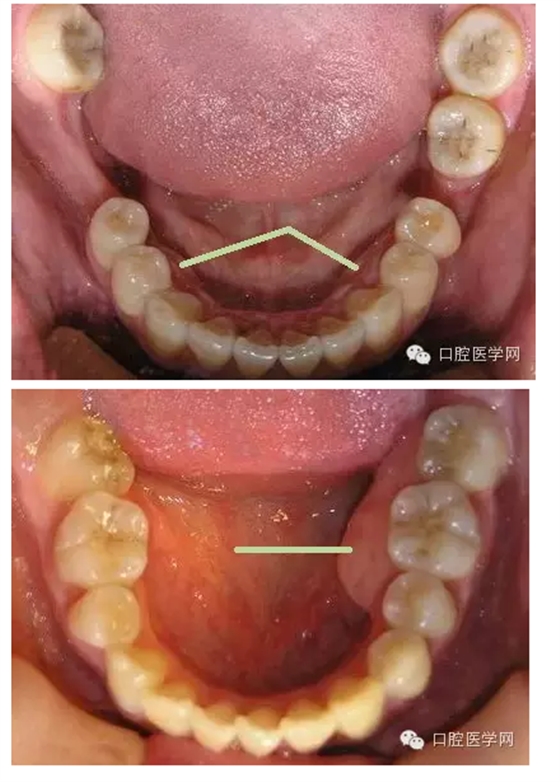

在臨床上我們需要把牙槽骨增生和骨隆突區(qū)分開來,骨隆突是在頜骨上的生理性骨性突起,并不是一個(gè)疾病癥狀,也不是疾病的表現(xiàn),比如舌側(cè)骨隆突、上頜骨骨隆突、下頜隆突是在第三磨牙和雙尖牙舌側(cè)的一個(gè)生理性突起。